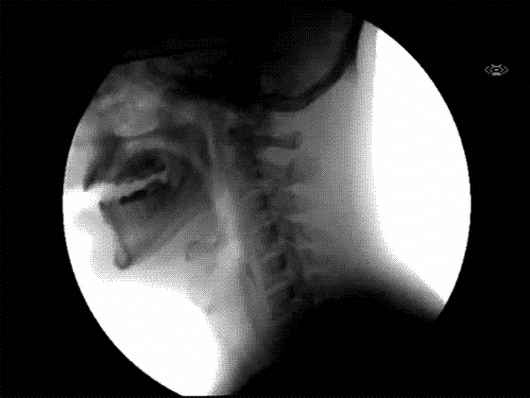

La segunda fase de este viaje es conocido como deglución, aquí los alimentos triturados y mezclados con la saliva (al que llamaremos Bolo alimenticio a partir de ahora) tienen su pasaje de la boca al esófago pasando por la Faringe:

La Faringe es una estructura que ayuda al bolo alimenticios a seguir su camino por el Tracto digestivo. Pero también impide el ingreso del mismo por las vías respiratorias, y así evitar el peligro de asfixia. Ésta fase es de transporte y absorción inicial de agua.